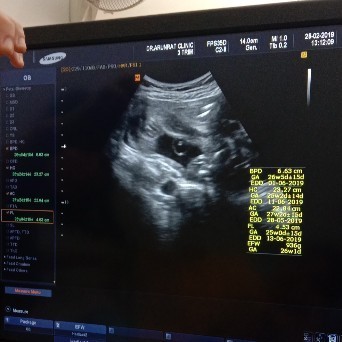

ซาวตอน 21w 4d จ้า หมอบอกได้ผู้หญิง แต่หมอที่นี้เคยมีประวัติซาวผิดบ่อย ขอคนดูเป็นคอนเฟริมน่อยจ้าา

ผญ.ล้าน%ค่ะ อ้าขาแบบไม่หนีบขาด้วย

คิดว่าหญิงแน่นอนคะ อ้าขาด้วย

ราบเรียบแบบนี้ ผู้หญิงนะคะ